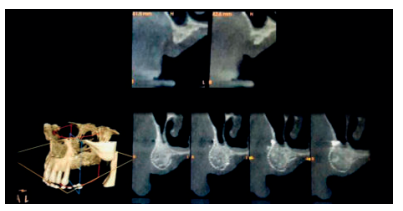

Todo esto se confirma en el momento de la intervención para la inserción de los implantes (Figura 9). Tras la retirada de los tornillos de osteosíntesis y de la micromalla se observa un buen aislamiento de los tejidos blandos, así como un adecuado mantenimiento del espacio, consiguiendo una integridad estructural con un tejido óseo estable, sangrante y bien incorporado al tejido huésped. El hueso regenerado disponible, tras la exploración clínica, se corresponde con un hueso tipo D2 (criterio de calidad ósea de Misch 2009).

Teniendo en consideración los criterios de calidad/cantidad ósea mencionados, se podrá comenzar con la planificación del tratamiento rehabilitador con los implantes dentales deseados, ya que se dispone de la máxima superficie de osteointegración posible sobre un hueso de buena calidad. En la preparación del lecho óseo receptor se usó un fresado secuencial (900-1100 rpm) y posterior colocación de implantes dentales con una correcta estabilidad primaria (Figuras 10 y 11).